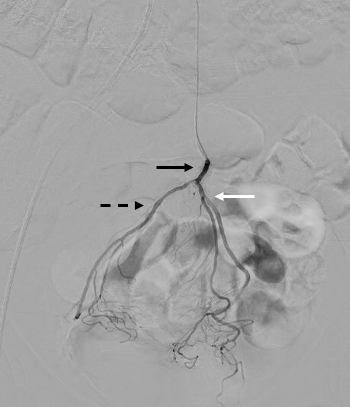

Aortography was performed with a 5F pigtail catheter positioned at L3 to identify the origin of the inferior mesenteric artery and its branches. Replacement of the 5F pigtail catheter was done with a 5F curve 2 Simmons catheter. Selective catheterization of the inferior mesenteric artery was performed in a posteroanterior view, followed by angiography with identification of the superior rectal artery (Figure 1).

Super-selective catheterization of the superior rectal artery was done with a Renegade STC microcatheter (Boston Scientific) and a Fathom-16 steerable guidewire (Boston Scientific) (Figure 2), followed by superselective catheterization of the branches of the superior rectal artery. Embolization of the branches was performed in their middle and distal thirds with Interlock-18 controlled-release fiber microcoils (Boston Scientific), 1 to 2 units per branch. See Figure 3 for control angiography demonstrating branch occlusion.